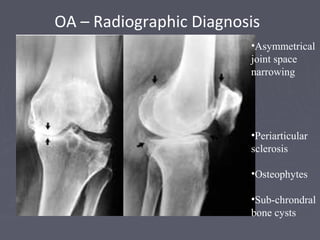

OA – Radiographic Diagnosis

•Asymmetrical

joint space

narrowing

•Periarticular

sclerosis

•Osteophytes

•Sub-chrondral

bone cysts

Asymmetrical joint spacenarrowing from loss of articular cartilage The medial (inside) part of the knee is most commonly affected by osteoarthritis. OA – Radiographic Diagnosis

OA – RadiographicDiagnosis •Asymmetrical joint space narrowing •Periarticular sclerosis •Osteophytes •Sub-chrondral bone cysts